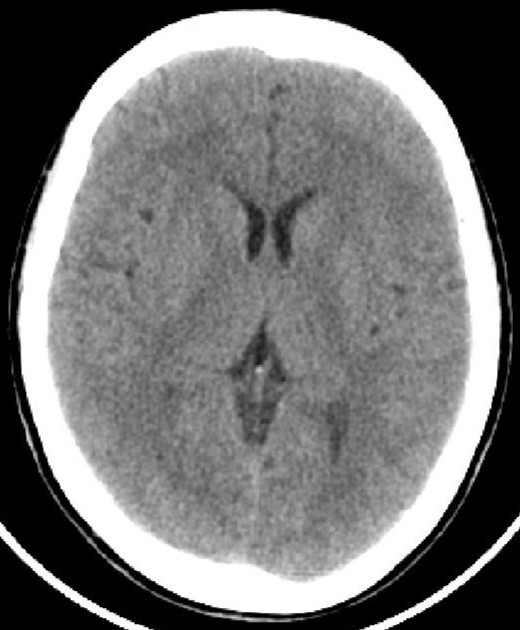

正常头颅CT          头颅CT示脑积水